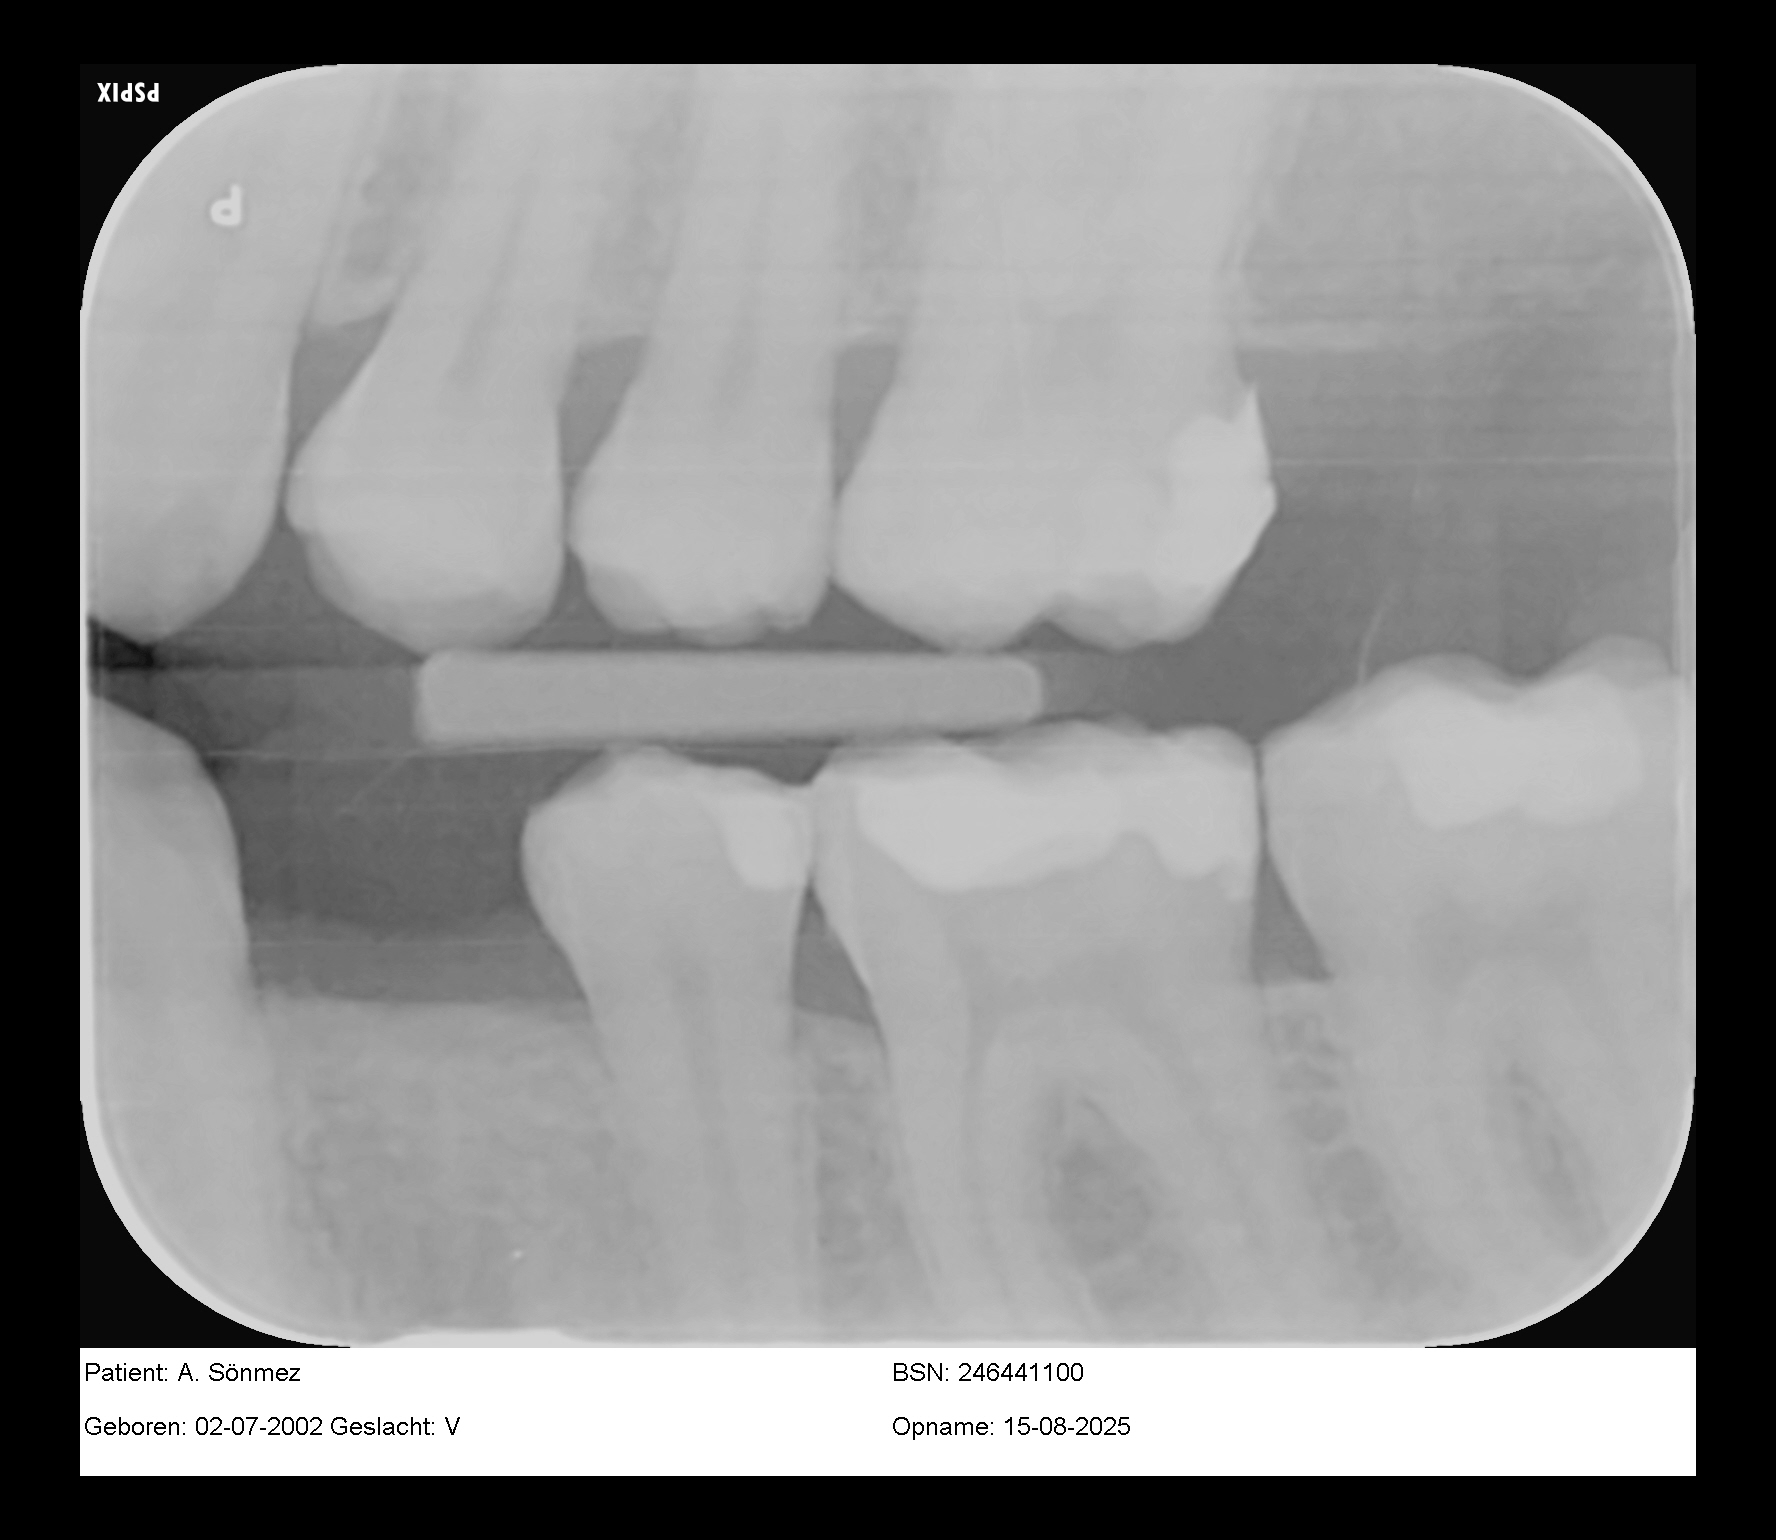

Dit zijn trouwens de foto's…

Dit zijn trouwens de foto's die vandaag zijn gemaakt!